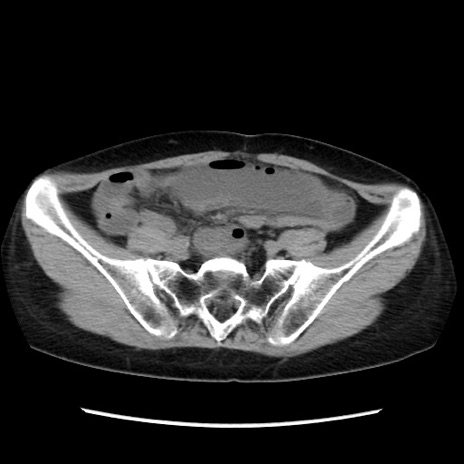

冠状断像